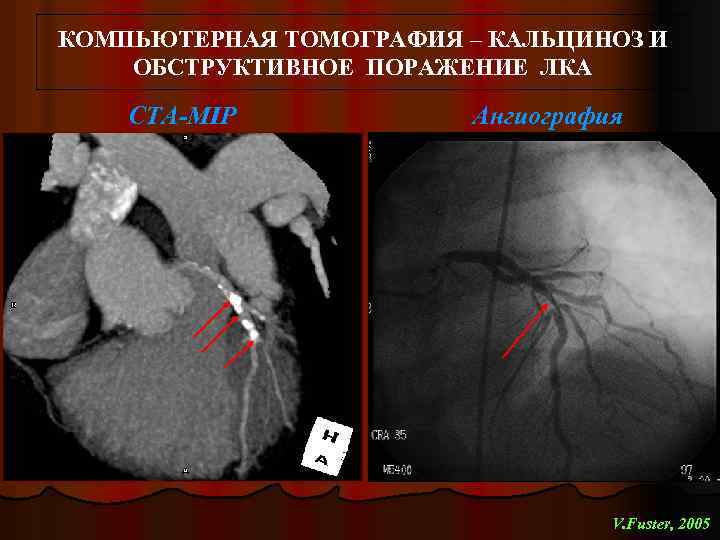

Анатомия коронарных артерий: КТ-изображения